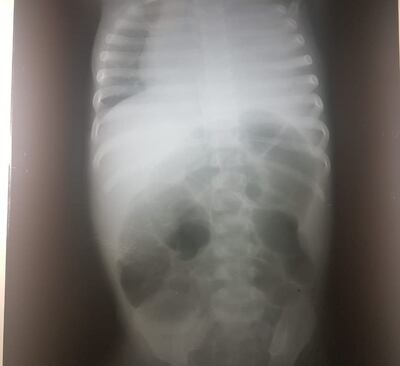

El nosocomio de esta ciudad no cuenta con el equipamiento necesario para tratar una neumonía que se complicó a raíz de un derrame pleural, es decir, acumulación de líquidos en los pulmones. La niña necesita un procedimiento que consiste en la colocación en un tubo de drenaje y que sólo un cirujano infantil lo podía hacer, según comentó el médico tratante.